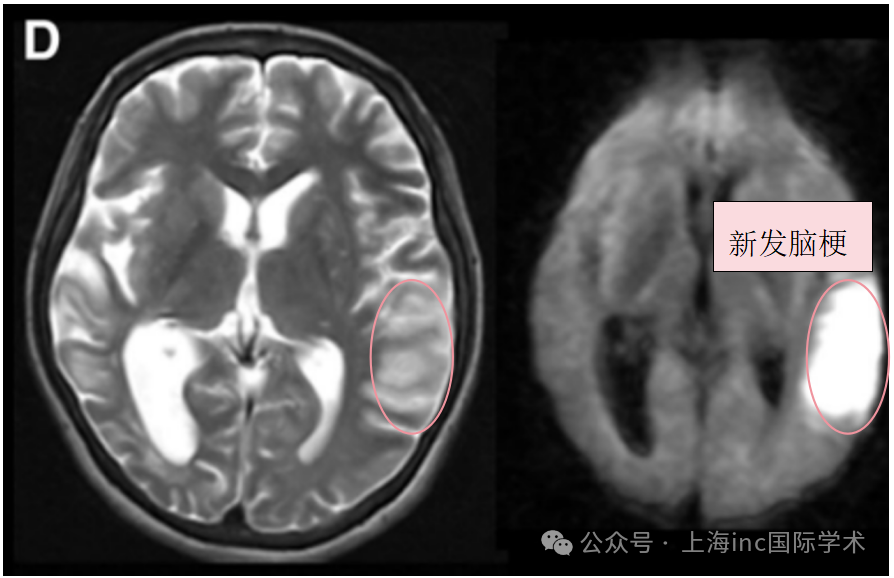

术前T2、DWI序列显示左额叶新发展的脑梗死。

入院3天后术前T2、DWI序列显示左侧颞叶进一步新发脑梗死。